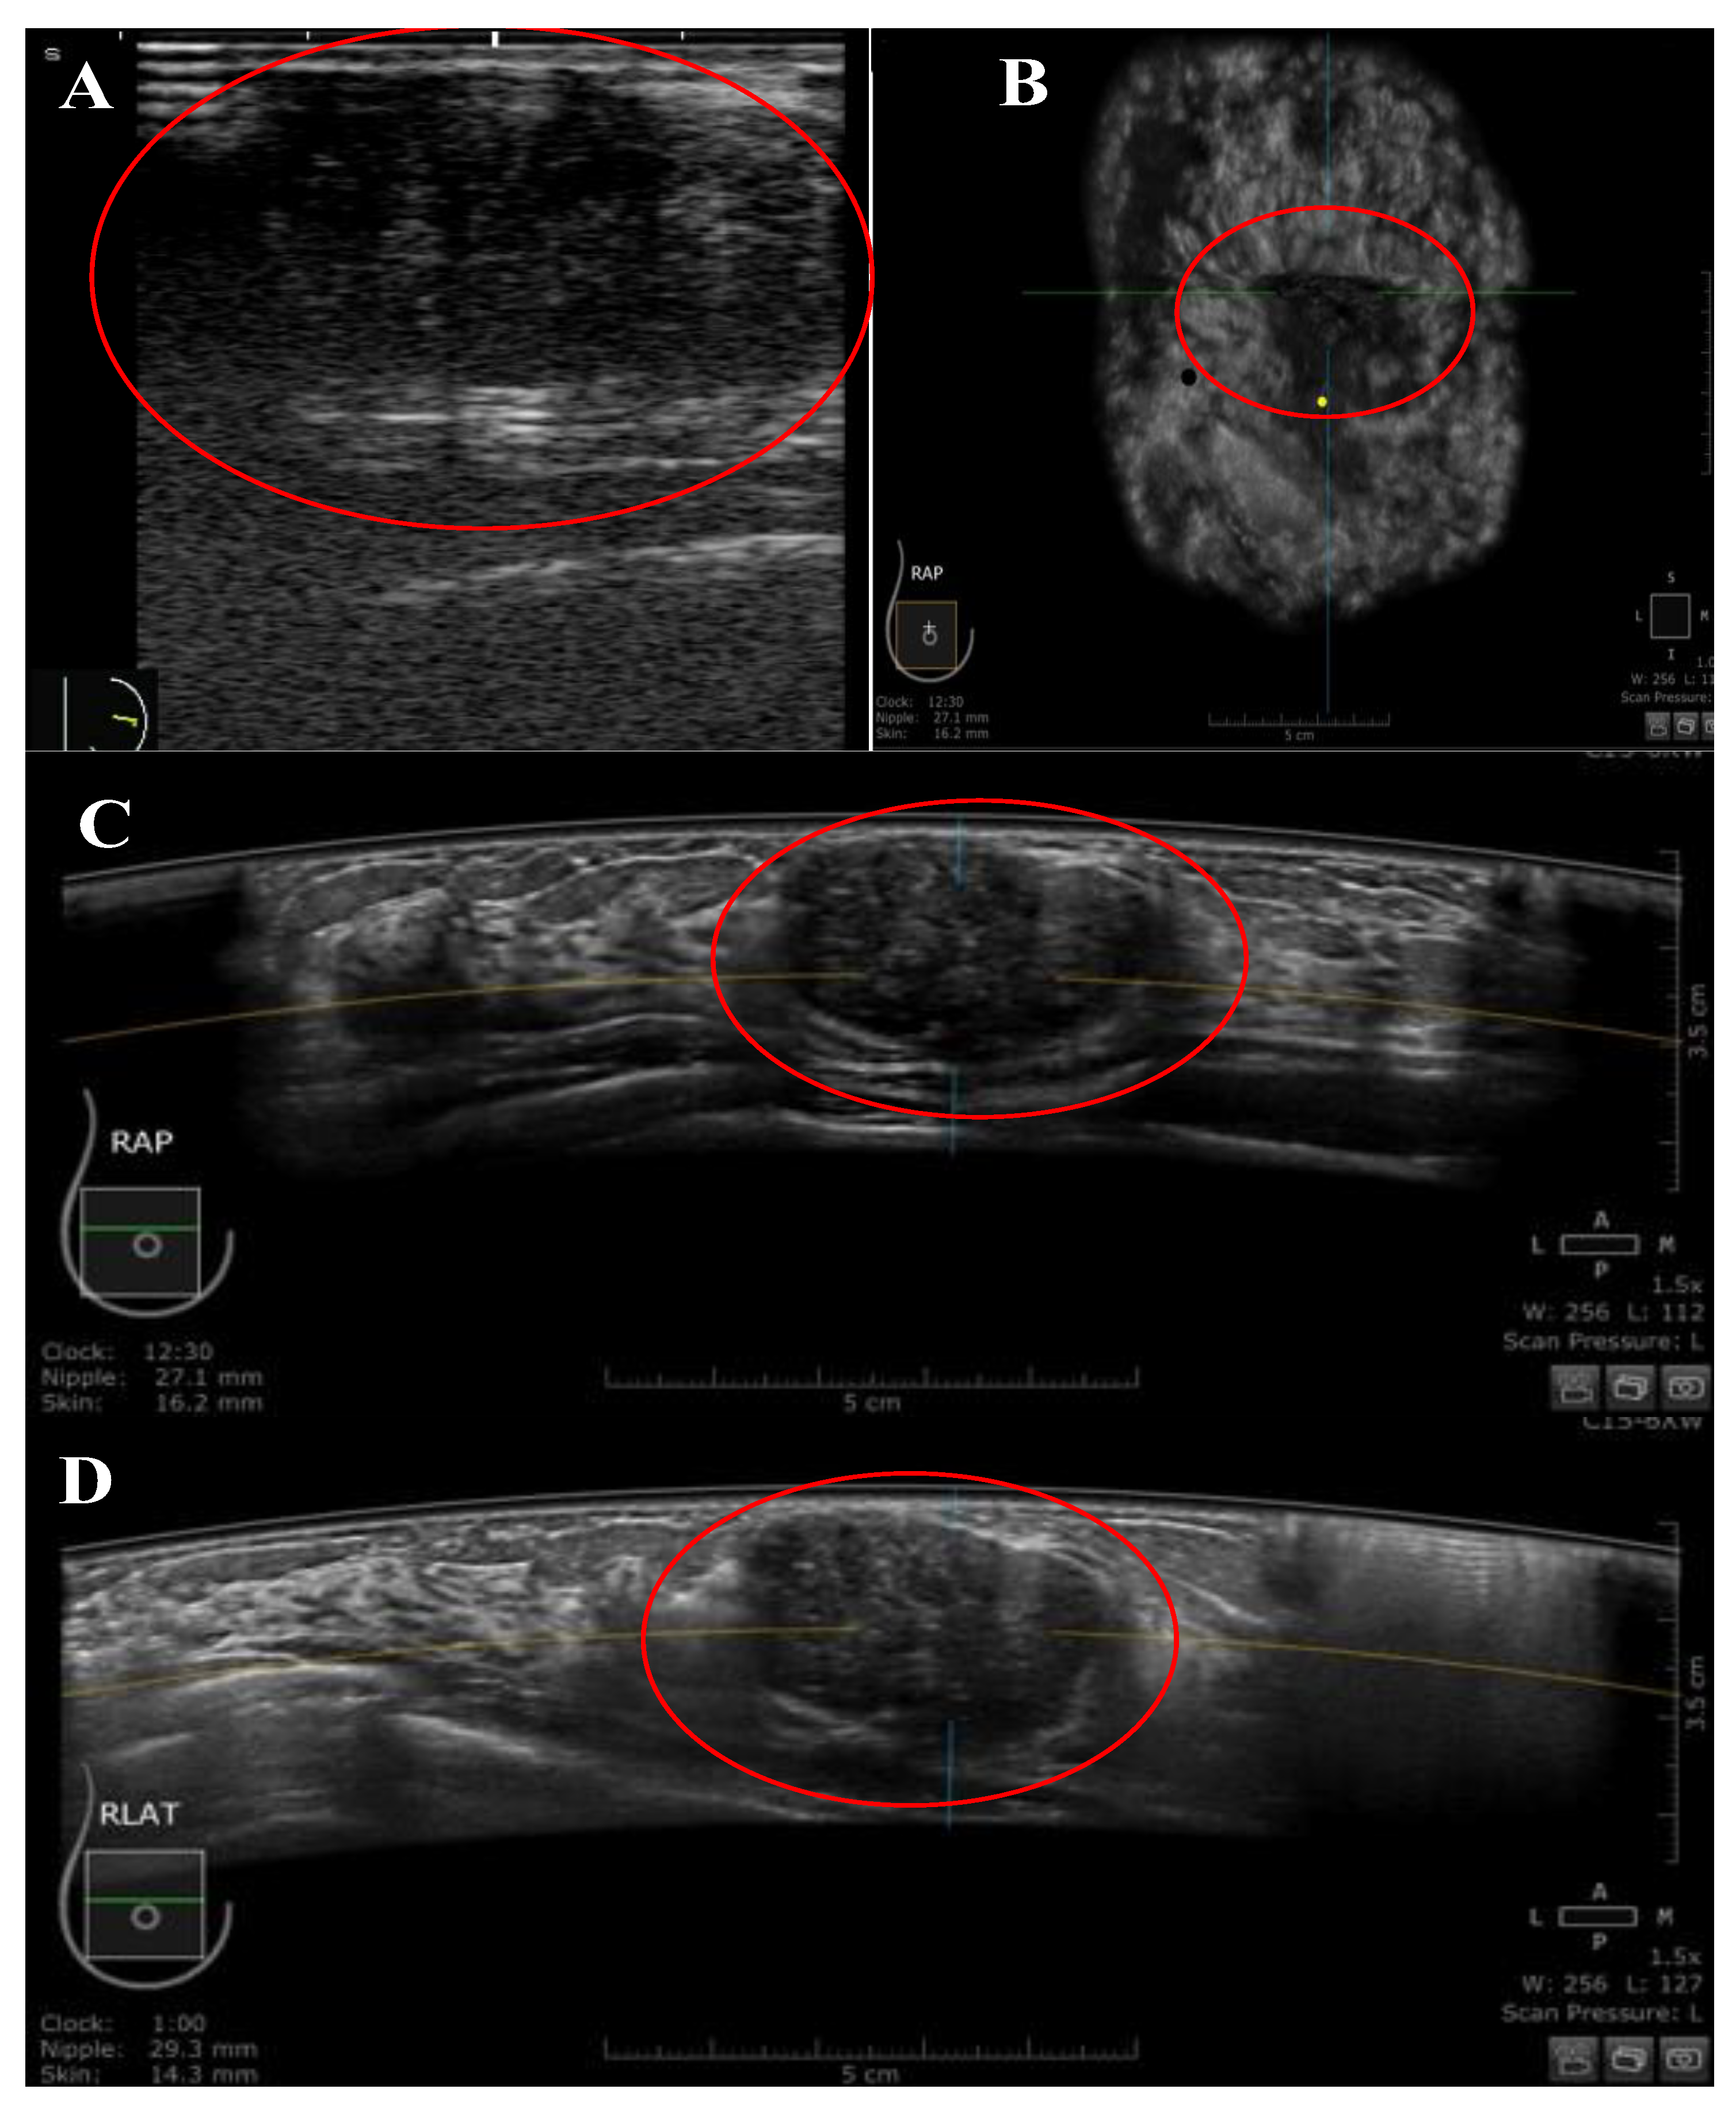

2.2. HHUS

2.3. ABUS